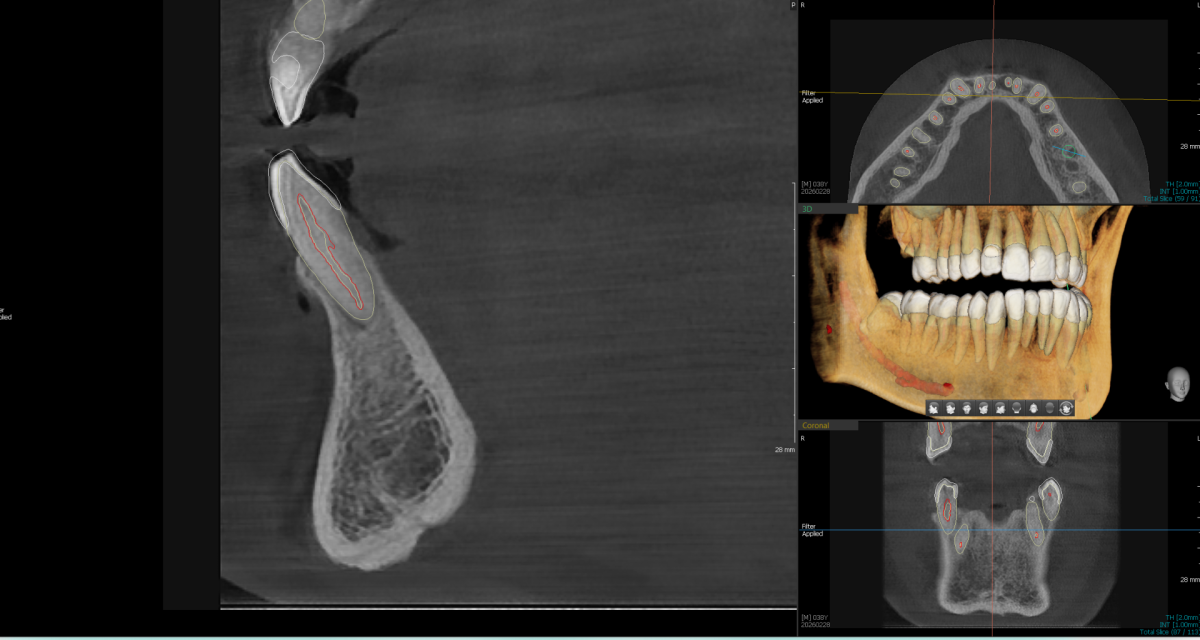

3D snimanje zuba (Cone Beam Computed Tomography) je revolucija u stomatološkoj radiologiji. Za razliku od klasičnog 2D ortopana, 3D snimak generiše trodimenzionalni model zuba, vilica, sinusa i koštanih struktura.

Sigurnost: Stomatolog vidi tačan položaj nerava i sinusa, čime se rizik od komplikacija svodi na minimum.

Vidljivost bez preklapanja: Otkriva anatomske detalje (poput dodatnih kanala korena) koji su na standardnim snimcima često skriveni.

Merenje u realnim proporcijama: Neophodno za precizno planiranje dentalnih implantata.

- Implantologija: Procena gustine kosti i planiranje pozicije implantata.

- Planiranje ugradnje implantata, oralno-hirurške intervencije poput sinus lifta i koštanih augmentacija, kao i kompleksna protetska rekonstrukcija. Snimak sadrži sve podatke o prostornim odnosima zuba, sinusa i mandibularnog kanala — u formatu, kompatibilnom sa vodećim softverima za planiranje.